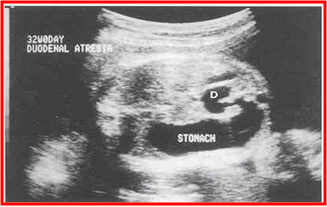

◇ 产前诊断

胎儿超声

羊水过多 胃及十二指肠近端扩张

十二指肠闭锁--双泡征(Double bubble sign)